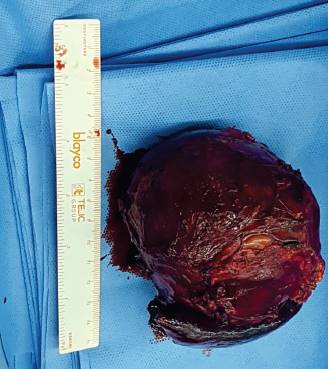

En el procedimiento quirúrgico se logró la resección completa de la tumoración y del polo inferior de bazo por presentar adherencias a cápsula esplénica. Procedimiento sin complicaciones. En el estudio macroscópico la pieza de resección pesó 330 g; al corte era quística con contenido friable, pardo-rojizo oscuro (Figura 2). Las secciones histológicas mostraron amplias áreas de necrosis y hemorragia entre las que se reconocía una proliferación celular atípica que se disponía en patrón pseudopapilar con células poco cohesivas, poligonales, de mediana talla; sus citoplasmas eran claros con ocasionales glóbulos hialinos (Figura 3). Se evidenciaron núcleos con hendiduras y cromatina en grumos, se observaron escasas mitosis típicas. El estroma presentaba áreas hialinizadas, acúmulos de macrófagos espumosos y escasas espículas de colesterol (Figura 4). Las técnicas de inmunohistoquímica mostraron positividad para enolasa, CD56, Fli-1, betacatenina (Figura 5) y vimentina, siendo negativo para sinaptofisina y cromogranina. Basados en estos hallazgos se realizó diagnóstico anatomopatológico de tumor sólido pseudopapilar de páncreas. Los bordes de resección y el parénquima esplénico se encontraban libres de lesión.

Figura 2: Pieza de resección de tumor pancreático compuesta por un sector ovoideo quístico de color pardo rojizo y un fragmento de parénquima esplénico adherido.